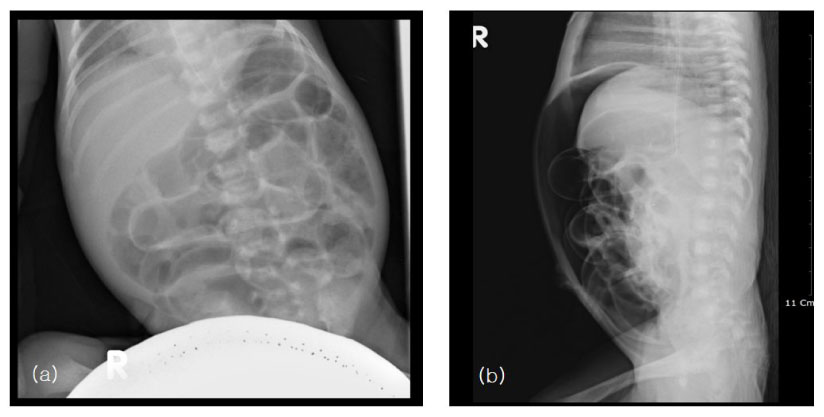

Fig. 1

Preoperative supine(a) and cross-table lateral(b) abdominal X-ray show distension of bowel loops and free air in the peritoneum.

Fig. 1 Preoperative supine(a) and cross-table lateral(b) abdominal X-ray show distension of bowel loops and free air in the peritoneum.